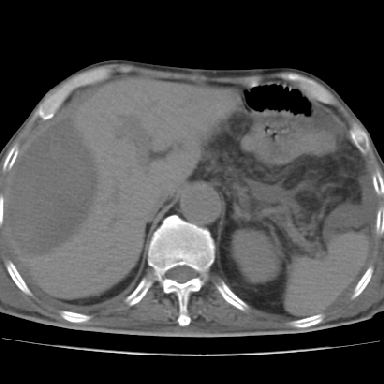

以下是引用qian在2006-12-4 19:11:00的发言:[br]胸腔和腹腔内均见有液性影,肝上极包膜下有一较大椭圆形低密度影,密度均匀,边缘清晰,结合病史考虑术后肝脓肿并胸腹腔积液。

以下是引用chry3在2006-12-4 21:05:00的发言:[br]应该往上扫几层,我考虑膈下脓肿。[br]大家考虑:胃部手术怎会造成肝内脓肿,隔下脓肿到是会造成的